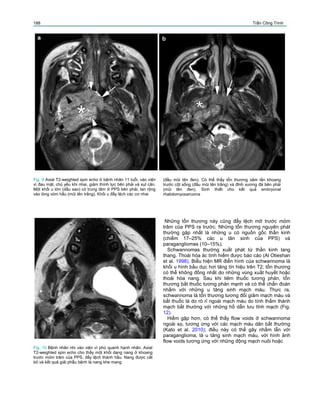

Fig. 13 Bệnh nhân tuổi thiếu niên, tình cờ phát hiện khối tổn

thương cạnh hầu; không có triệu chứng lâm sàng. Axial T2-

weighted spin echo image (a) cho thấy khối tăng tín hiệu, đẩy

lệch động mạch cảnh trong (đầu mũi tên) và tĩnh mạch cảnh

tronng (mũi tên) ra phía ngoài. So sánh với axial T1-weighted

không tiêm thuốc tương phản (b) coronal T1 có tiêm thuốc

tương phản (c) cho thấy tổn thương này bắt thuốc đáng kể.

Chẩn đoán phân biệt chủ yếu là hạch sau hầu bệnh lý, hoặc u

có nguồn gốc thần kinh từ chuỗi giao cảm. Phẫu thuật cho thấy

tổn thương từ chuỗi giao cảm, giải phẫu bệnh là

ganglioneuroma

Fig. 14 Axial T2-weighted (a) và T1-weighted spino echo có

tiêm thuốc tương phản (b) ở bệnh nhân vào viện vì phù dưới

hàm. Khối tổn thương thấy ở khoang sau mỏm trâm của PPS,

gây tách rời động mạch cảnh trong (đầu mũi tên đen) và tĩnh

mạch cảnh trong (bị chèn ép, mũi tên). Tổn thương cũng đẩy

lệch nhẹ động mạch cảnh ngoài (đầu mũi tên trắng) ra trước,

nhưng trung tâm tổn thương không nằm ở chỗ chia động mạch

cảnh. Bên trong tổn thương, thấy được nhiều dòng chảy trống

giống mạch máu, cho thấy tổn thương tăng sinh mạch. Những

dấu hiệu này phù hợp với khối u glomus vagale; tổn thương

sau đó được cắt bỏ và được xác định chẩn đoán trên giải phẫu

bệnh.

Fig. 19 Bệnh nhân lớn tuổi vào viện vì đau họng bên phải.

Khám lâm sàng cho thấy phù hạnh nhân, không sốt. Axial

CT có tiêm thuốc tương phản (a) cho thấy khối tổn thương

lớn chứa dịch (dấu sao) ở khoang trước mỏm trâm của

PPS, điều này có thể gây nhầm lẫn với abscess quanh hạnh

nhân. Tuy nhiên, có thể thấy thành phần đặc (đầu mũi tên)

với đóng vôi nhỏ ở mặt ngoài của tổn thương, gợi ý khối u

xuất phát từ thùy sâu của tuyến mang tai. T1-weighted có tiêm

thuốc tương phản (b) cho thấy rõ hơn thành phần đặc của khối

u ở guyến mang tai (mũi tên). Chọc hút qua miệng thành phần

nang cho thấy dịch xuất huyết. Bệnh nhân không theo dõi tiếp

tục được; tổn thương này phù hợp nhất với pleomorphic

adenoma có xuất huyết ở PPS

tĩnh mạch dẫn lưu. Nếu cần thiết, chẩn đoán phân

biệt có thể thực hiện bằng tiêm thuốc tương phản

động học: schwannoma gần như luôn luôn bắt thuốc

chậm, tăng dần; trong khi paragangliomas bắt thuốc

nhanh.

Paragangliomas (còn gọi là glomus tumors) xuất

phát từ các tế bào hóa thụ cảm, về cơ bản hiện diện

ở ba vị trí khác nhau: ở ngang mức nodose ganglion

của thần kinh lang thang, ngay phía dưới đáy sọ

(vagal paraganglioma), ở ngang mức chỗ chia động

mạch cảnh (carotid paraganglioma) và ở ngang mức

lỗ tĩnh mạch cảnh trong (jugular paraganglioma). Tổn

thương bắt thuốc mạnh, trên MR, có hình ảnh ‘salt and

pepper’ khá điển hình: điều này do sự hiện diện của

những mạch máu có đường kính ngoằn ngoèo (được

phát hiện nhờ flow voids) bên trong khối u (Fig. 14). Tuy

vây, đặc điểm này có thể khó thấy hoặc biến mất, đặc

biệt ở những tổn thương nhỏ với những mạch máu có

đường kính nhỏ ưu thế (Som and Curtin 1995). Những

khối u thân động mạch cảnh thường tách động mạch

cảnh trong và cảnh ngoài và có thể lan lên trên vào

PPS. Vagal paraganglioma có trung tâm ở khoang sau

mỏm trâm của PPS; ít khi đến chỗ chia động mạch

cảnh. Jugular paraganglioma có trung tâm ở lỗ tĩnh

mạch cảnh, thường bào mòn xương xung quanh và lan

vào tai giữa (Swartz et al. 1998). CT và MR cho phép

chẩn đoán chính xác glomus tumors trong hầu hết các

trường hợp.